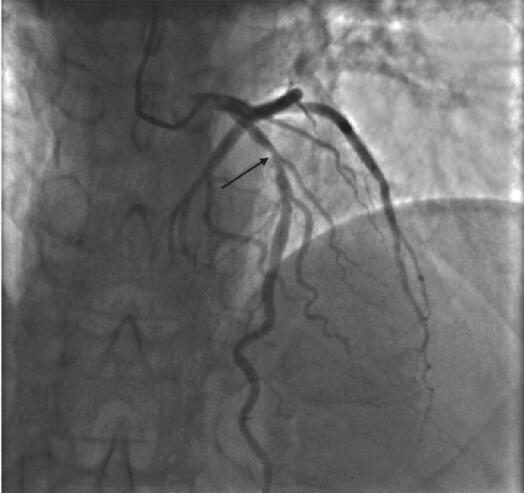

冠脉呈左冠优势型,前降支近段狭窄,程度约80%;中段狭窄,程度约30%;第二对角支开口狭窄,程度约30%。回旋支未见明显病变征象。右冠细小,近段、中段狭窄,程度约40%(图11-4)。

图11-4 缓解时ECG所见